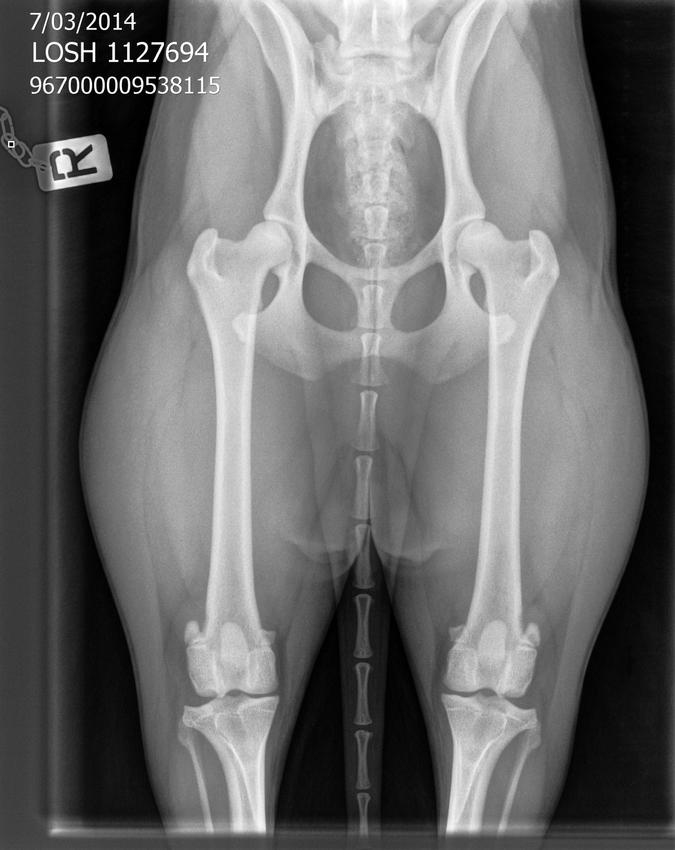

heb de eerste foto binnen gekregen van de DA. Er zijn problemen met het verzenden naar KKUSH. Daarom duurt het al een tijdje voor ik een rekening krijg. Hier dus de heupen (en de dikke billen) van Sky :D

Wat leuk om te zien o__o ze heeft een mooie euhm...gebeente? Ziet er op het eerste zicht erg netjes uit, niet dat ik er veel van ken. Die botjes in dat staartje~ <3

De dierenarts zei dat het er heel goed uit zag. Maar ze was zeer onder de indruk van de hoeveelheid spieren die sky al had :D En ik moet zeggen, elke keer als ik die foto opnieuw zie, denk ik dat het een foto is van een dikbilrund ![]()

De kommen zijn niet heel diep, maar het ziet er verder wel goed uit.

Ze heeft al redelijk wat bespiering, maar ook nog wel wat "vetrandjes"....

Misschien leuk om het verschil te zien met onze reu Eazy (HD A NB 40).

de uitslag is binnen!

Resultaat:

HD: B

ED 0:0

SD 0:0

Zo blij!! En Sky, die snapt er helemaal niets van! :D